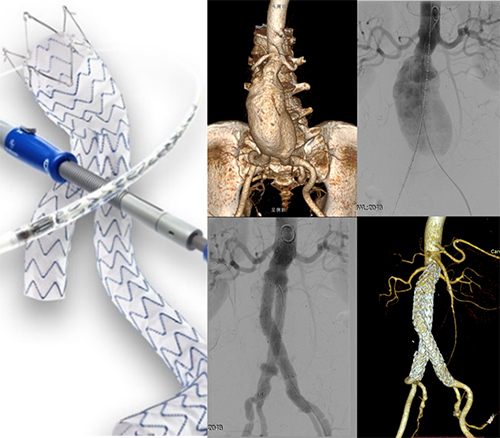

腹主动脉瘤腔内修复术治疗肾下腹主动脉瘤(EVAR)

主动脉疾病一旦累及到分支动脉(弓上动脉、内脏动脉)都属于复杂胸腹主动脉病变,在做腔内治疗的时候需要在覆膜支架封闭隔绝瘤体的同时完成主动脉分支的血流重建。目前,医生台上改制开窗-分支支架技术是主流的方法,也是临床治疗的难点和热点,它可以有效降低传统胸腹联合切口开放手术、内脏动脉去分支技术的围手术期并发症和死亡率,尤其是使得高危高龄、手术耐受力差的患者得到有效救治的机会。这项技术是最复杂的主动脉腔内手术之一,个体化制作开窗-分支支架技术难度高,既要根据每个病变的解剖特点准确开窗和缝制分支,更要在手术中将窗口对准要重建的分支动脉,独立开展该项技术需要医院综合实力支撑(人员、场地、设备)。

支架经个体化改制后的开窗-分支支架